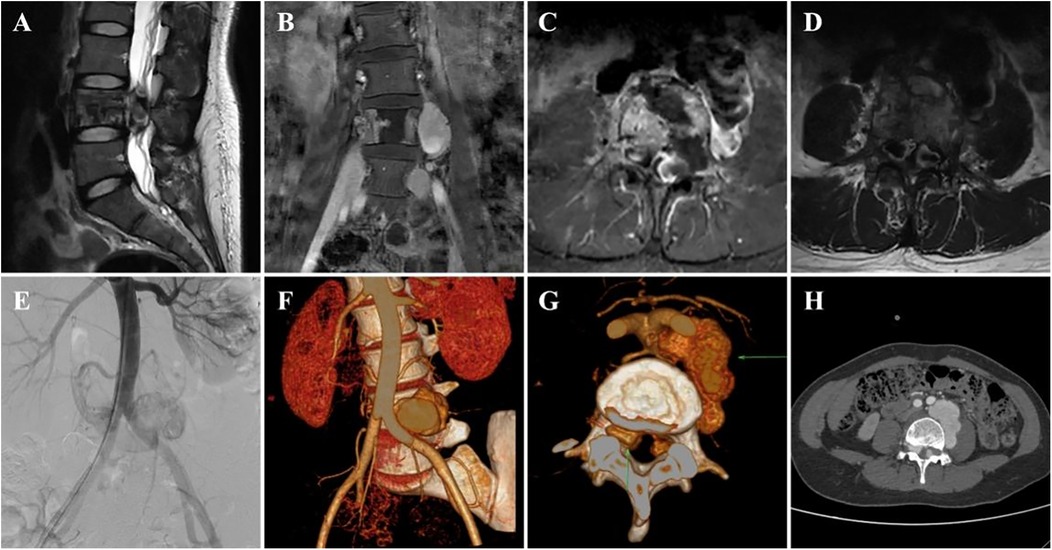

The patient's pain in both lower extremities was completely relieved postoperatively. Drug treatment included methylprednisolone and mecobalamin for nerve repair and ibuprofen and pregabalin for pain management. Imaging reexamination with DSA (Figures 2A,B), x-ray (Figures 2C,D), CTA (Figures 2E,F), and MRI (Figures 2G,H) scans confirmed that the intraspinal and paraspinal aneurysms had completely disappeared. The rehabilitation treatment plan (implemented 2 weeks after surgery) included lower extremity motor function training, balance ability exercise, medium frequency pulsed electrical stimulation therapy, pneumatic therapy, and biofeedback training for urinary and fecal functions.

Figure 2

A series of eight medical images labeled A to H. A shows an angiogram of a blood vessel. B displays a coiled vascular structure. C and D are X-rays of the spine with surgical hardware. E depicts a 3D vascular reconstruction. F shows a CT scan with bright surgical materials. G is a sagittal MRI of the spine. H presents an axial MRI of the spine showing the spinal canal and surrounding structures.

Figure 2. Postoperative imaging data of the patient. (A,B) postoperative DSA images, (C,D) postoperative x-ray anteroposterior and lateral views, (E,F) postoperative CTA images, and (G,H) postoperative MRI images.

The pain in both lower limbs disappeared postoperatively, and rehabilitation training was initiated 2 weeks later. After 3 months of rehabilitation, follow-up examinations revealed that the lower-limb muscle strength recovered to grade Ⅲ and that the residual bladder urine volume was <50 ml. Moreover, MRI revealed complete relief of spinal canal compression with no recurrence.